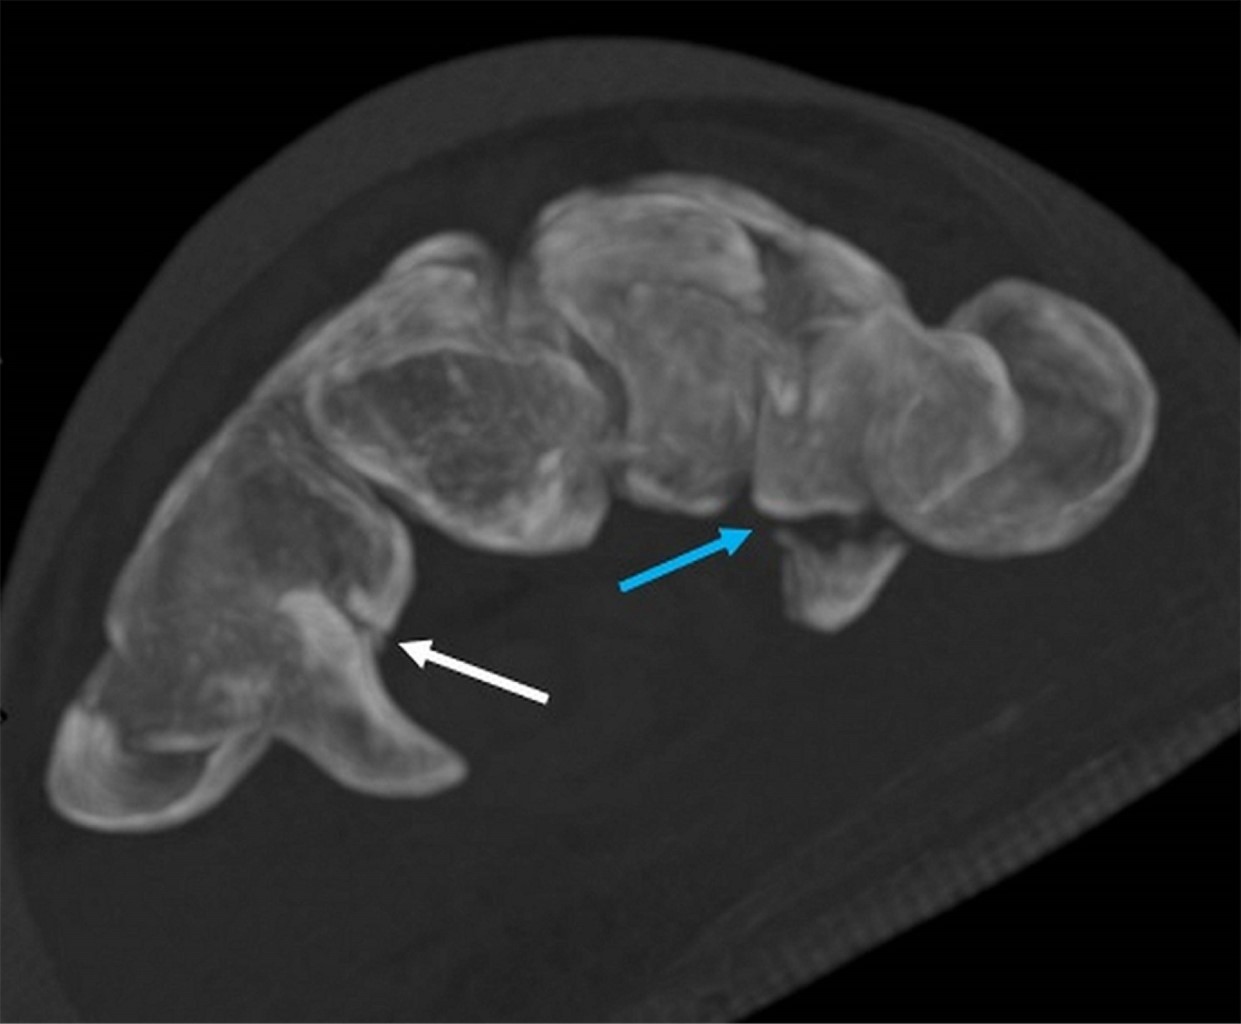

Computed tomography (CT) scan reveals a hamate bone fracture without apparent misalignment (Figure 1) and a type I trapezium tuberosity base fracture (according to Walker's classification) with a 0.2 cm fragment distance, without significant misalignment [ICD 10-S62] (Figures 2 and 3).

Trapezium tuberosity fractures have been classified into two main types: type 1, located at the tuberosity base where there is direct trauma to the base, as in the described case, and type 2, located at the tuberosity tip where there is avulsion of the carpal transverse ligament from the tip.1,2 Type 2 fractures are reported to have a higher risk of nonunion and may be associated with hamate hook fractures. Both fractures occur with the hand extended.1 Crushing injuries are frequently associated with trapezium tuberosity fractures, while hamate body fractures are commonly caused by direct impacts, such as those from tennis racket handles, golf clubs, and baseball bats.7

Figure 3